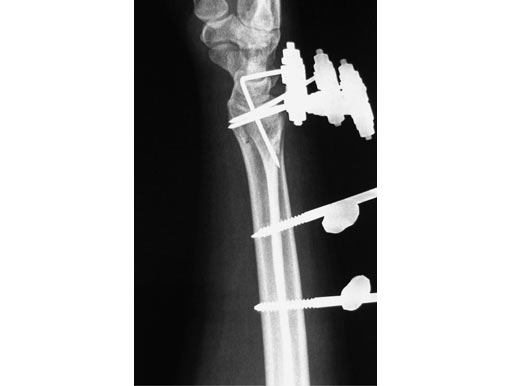

Treatment of fractures of the distal radius has been proven to be advantageous if spanning of the wrist joint is avoided. This allows for greater motion throughout the treatment resulting in improved range of motion, grip strength, and dexterity. The nonspanning Distal Radius Fixator provides such a nonbridging external fixator, creating a low-profile frame for increased patient comfort and the ability to perform daily activities.

The nonspanning Distal Radius Fixator consists of a small adjustable clamp, nonspanning, MR safe. It locks on to two 4.0 mm Schanz Screws spaced 20 mm apart. The 4.0 mm carbon fiber rod slides into a through hole in the clamp with a set screw tightening point to established the desired length. A ball joint in the clamp then provides for ulnar/radial as well as volar/dorsal deviation of the rod. To create lower profile frames, the nonspanning Distal Radius Fixator includes three shorter length Schanz screws65 mm lengths in both 4.0/2.5 mm size (with a trocar tip) and the 4.0/3.0 mm size (with a self-drilling tip), and an 80 mm length in the 4.0/2.5 mm size (with a trocar tip).

The 4.0 mm curved carbon fiber rods match the axial curvature of the wrist. They are available in 60, 90, 120, or 180 arcs to be used for fixation of the distal fragment.

The 4.0 mm angled T-bar carbon fiber rods create the same angle as the curved rods, with the addition of a rod extending perpendicularly. The material allows a frame to be constructed with a rod centred on the dorsal aspect of the wrist without sacrificing the C-arm image in the dorsal/palmar view. The angled T-bar fiber rods will be available in 80 mm (length) 50 mm (width), 80 120 mm, 110 50 mm, and 110 120 mm. Both the curved and angled T-bar fiber rods can be used as part of a delta frame construct.

56-year-old female, accident at home